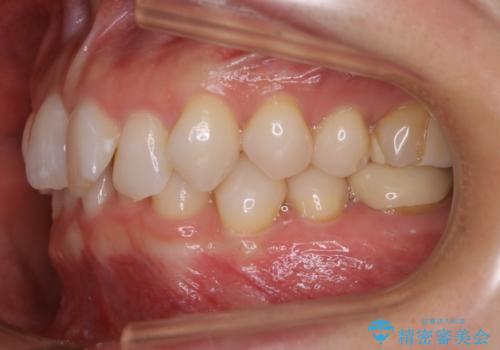

【抜歯】矯正治療とインプラントで正常な噛み合わせを実現

- 元々は矯正治療を主訴にご来院されました。

治療を始めるにあたり、精密検査を受けていただき全体の状況を把握したうえで矯正治療の計画を立てることとなりました。

その過程で左下の6番目の歯は治療が必要な状態であることが分かり、被せ物を外して内部を確認してみると根が破折してしまっていることが判明しました。

歯が深い位置で破折している場合は基本的には抜歯が選択されます。

様々な治療プランを患者さんと相談させて頂き、最終的にインプラントで噛み合わせを回復させていくこととなり、まず悪くなっている歯を抜歯することから開始しました。